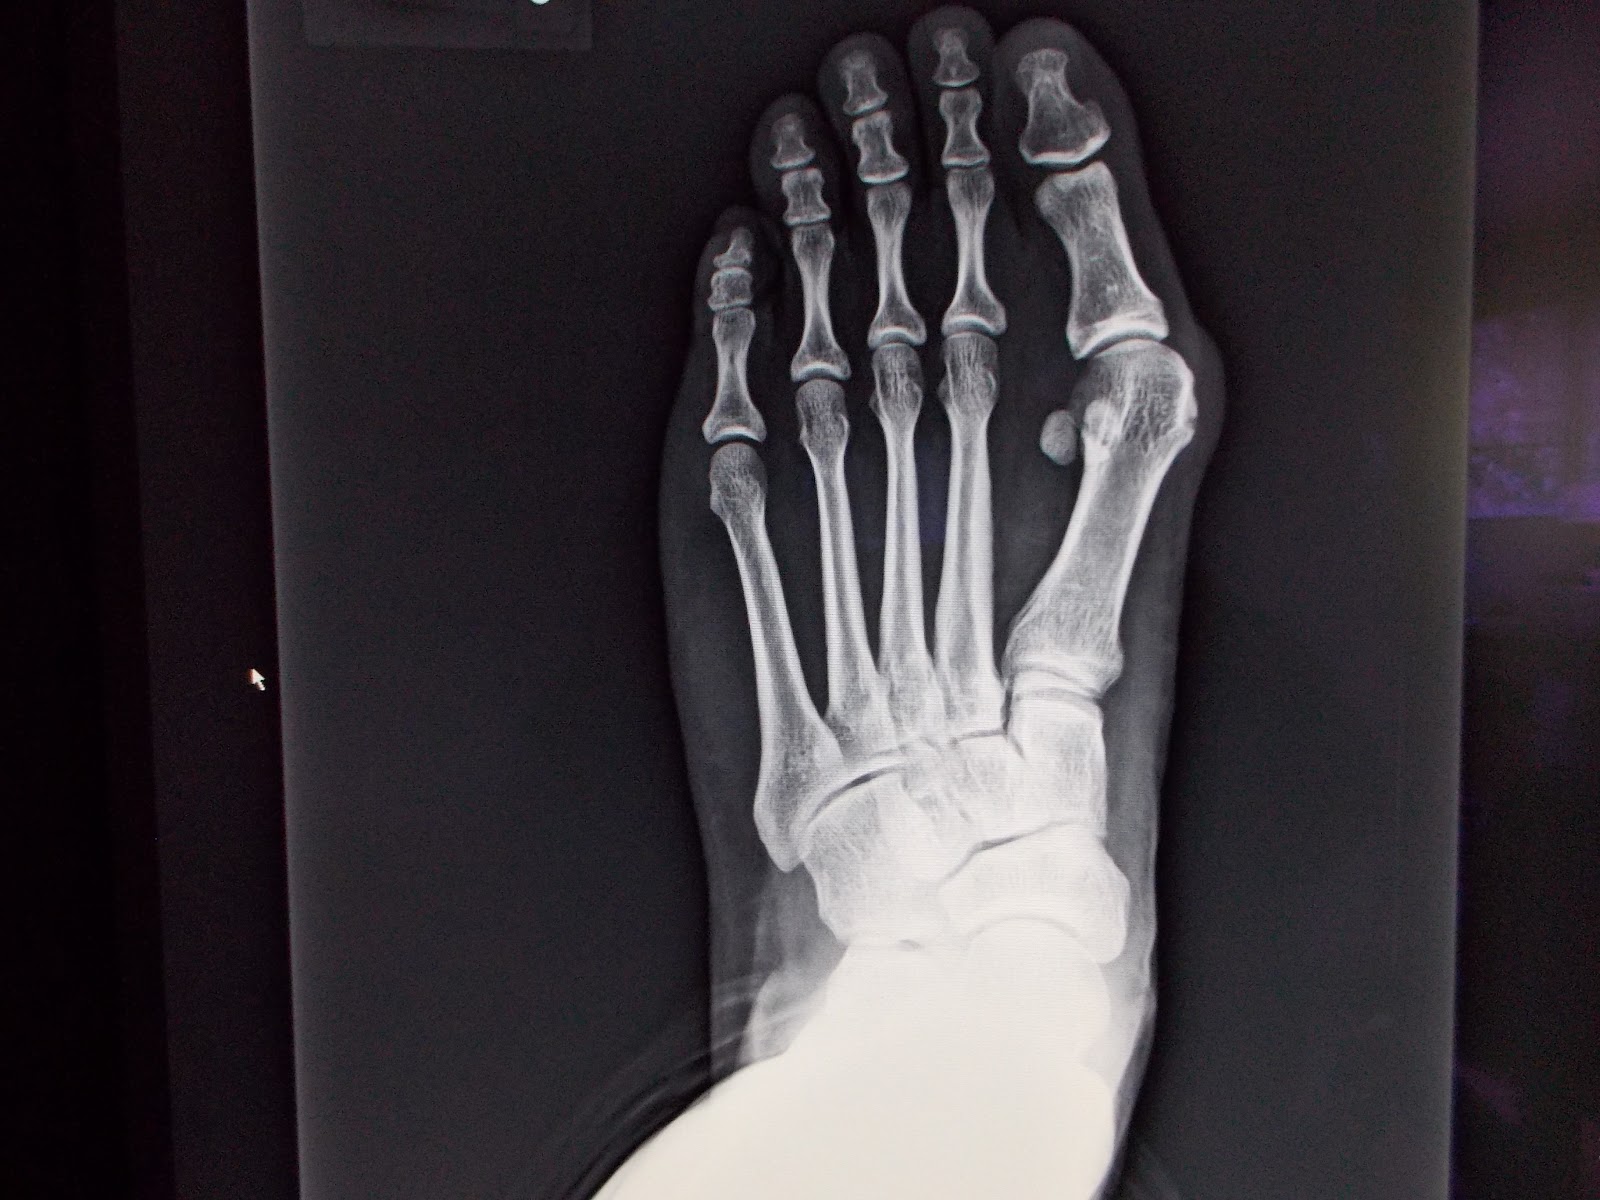

太緊的內收肌 肌腱,把大拇趾慢慢的向外拉,趾蹠關節也被拉成脫臼,產生關節滑液囊腫(即常稱的Bunion);或頂起鄰(第2)趾、或造成足底胼胝(雞眼),讓腳久站、走路、穿鞋疼痛。診斷上,除了看外觀外,還須照X-光,仔細評量趾-蹠交角、蹠-蹠交角的度數;趾-蹠關節 對位情形,及蹠底芝麻骨 (有2個) 脫位的程度……等,作為是否須手術治療的憑估。雖然,坊間有各式各樣的護具、矽膠墊、…..宣稱可復健矯正,但實際上沒有真正的效果,矯正還是要靠手術。

手術主要是作蹠底內收蹠肌 肌腱的鬆筋術,以消除肌腱的不當拉(張)力;在大部份年青小姐、早期外翻 (趾蹠骨交角)不厲害,鬆筋手術即有很好效果(圖3.)。